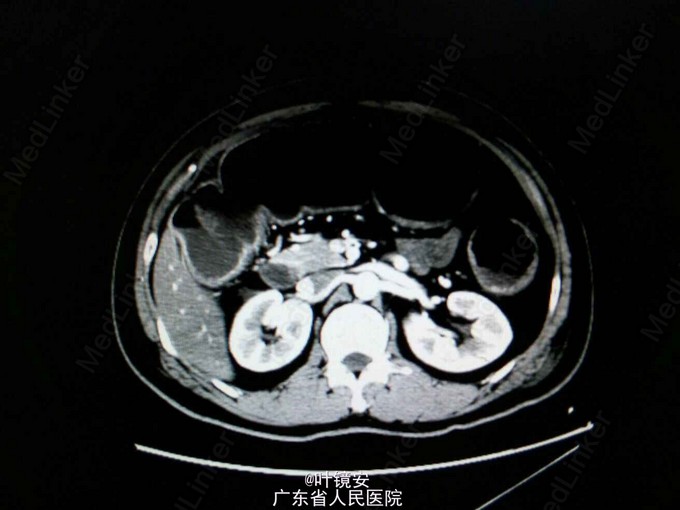

查体:心肺无特殊,腹部膨隆,无压痛以及反跳痛,肝脾触诊不满意,全腹叩诊鼓音,移动性浊音阴性,肠鸣音6次/分。辅助检查:实验室检查:血常规提示白细胞 11.13X10^9/L;大便常规提示隐血试验阳性、白细胞4+/HP、红细胞2+/HP;CRP 104.2mg/L;结核抗体、轮状病毒抗原、大肠杆菌检测等未见异常;肠镜提示距肛门15cm以上乙状结肠粘膜可见大片地图状的深凹黄苔溃疡,考虑乙状结肠炎症性改变。活检提示大肠粘膜呈慢性活动性炎,个别隐窝脓肿形成。全腹CT检查提示:乙状结肠改变,余结肠积气扩张,考虑炎性病变所致。复查腹平片提示结肠区异常,考虑肠道功能紊乱可能。

诊断:溃疡性结肠炎并中毒性巨结肠。 处理:内科行抗感染、胃肠减压、肛管排气等治疗无效。患者病情加重,腹胀加重,体温升高39.4℃,多学科会诊后,血气检查提示氧分压:54.9mmHg,调高吸氧浓度。请普外急会诊,行全结肠切除+回肠造口术。